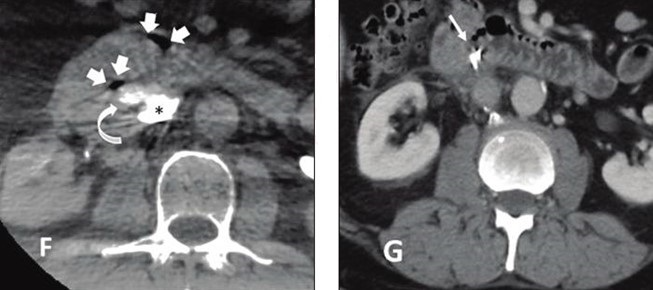

58-year-old patient referred for complex IVC filter retrieval after dwell time of 72 months. F, Axial image from cone-beam CT immediately following retrieval shows two foci of gas in retroperitoneum (white block arrows) and contained contrast extravasation (curved white arrow) from IVC (asterisk). G, Axial image from contrast-enhanced CT performed 1 day post-retrieval shows interval placement of hemoclips in duodenum (arrow), with no further extravasation evident. This was only patient in study sample who experienced major adverse event during complex retrieval.

At these specialized IVC filter referral centers—which employed interventional radiologists having expertise in such procedures—the complex retrieval success rate was 100.0%, with an adverse event rate of 11.2% and major adverse event rate of 0.8%. Ultimately, the only independent predictor of adverse events was prolonged filter dwell time ≥5 years (odds ratio=6.98).